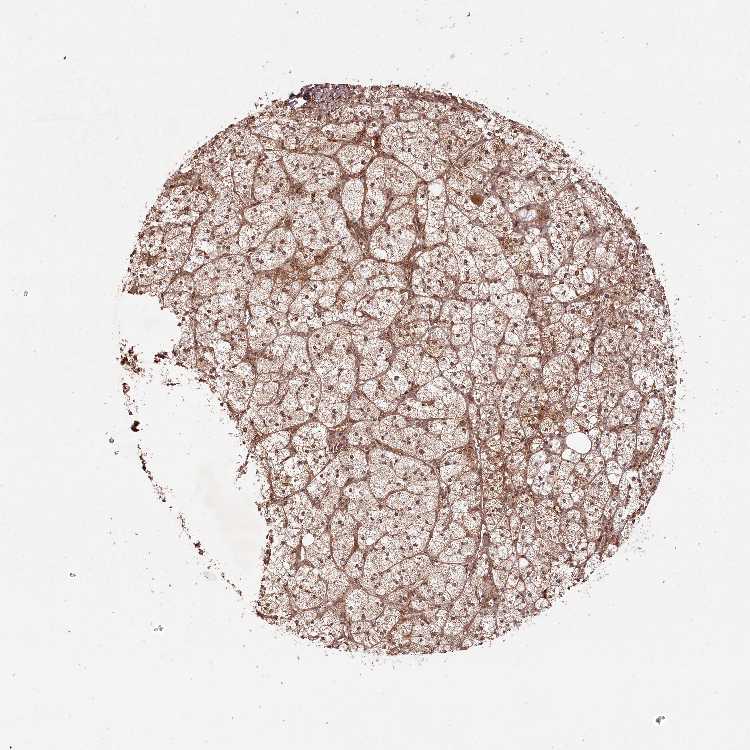

ADRENAL GLAND - Antibody stainingi

Antibody staining in the annotated cell types in the current human tissue is reported as not detected, low, medium, or high, based on conventional immunohistochemistry profiling in selected tissues. This score is based on the combination of the staining intensity and fraction of stained cells.

Each image is clickable and will lead to virtual microscopy that enables deeper exploration of all samples and also displays staining intensity scores, fraction scores and subcellular localization as well as patient and tissue information for each sample.

Antibody HPA037480

Glandular cells High